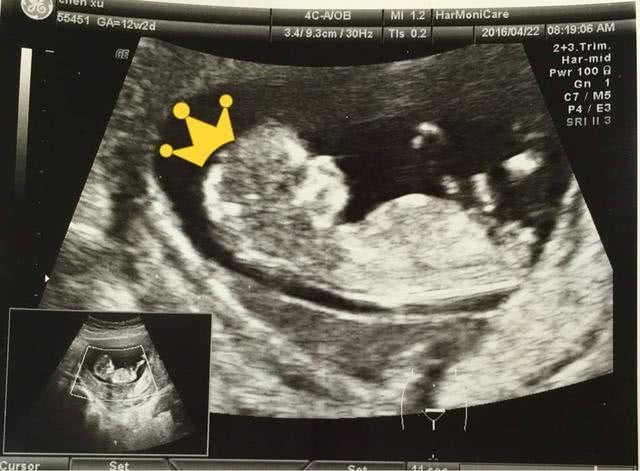

可是为了早早的排查唐氏儿,现在在孕11-14周的时分,医院还会给孕妈妈做一个叫做“NT”的查看。所谓“NT”便是胎儿颈部半透明膜,是通过超声波,来监测胎儿背侧软组织,和皮肤之间的厚度,来查看孩子是否患有唐氏综合征。由于唐氏儿的颈部软组织,一般会伴有水肿的发作,所以厚度会比正常孩子要厚。这或许是由于唐氏儿的染色体反常,导致心脏变形致使心功能衰竭,然后颈部血管发育不全导致的。

现在,NT被认为是排查唐氏变形最有用的手法,也是第一个的软指标的筛查,最佳的查看期便是在11-14周。由于11周之前的胎儿较小,且活动量少,很难监测到。可是14周之后,胎儿处于比较活泼的状况,也很难监测到。所以一般状况下,医师都会在11-14周为孕妈妈查看。

一般NT正常值小于2.5毫米,假如NT的成果显现胎儿颈部透明膜加厚,则阐明胎儿患唐氏儿的几率较大,需求进一步的查看。假如成果正常,在16-20周的时分,以防万一,孕妈妈仍然要进行唐筛,一旦发现,要在医师的主张下尽早停止妊娠。